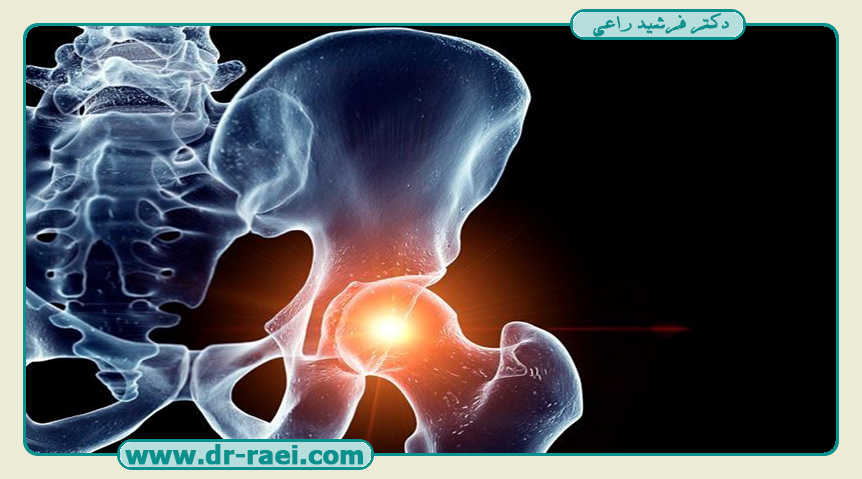

انواع شکستگی لگن از جمله آسیبهایی هستند که میتوانند تاثیر قابل توجهی بر حرکت، تعادل و کیفیت زندگی فرد بگذارند. این آسیبها معمولا در اثر